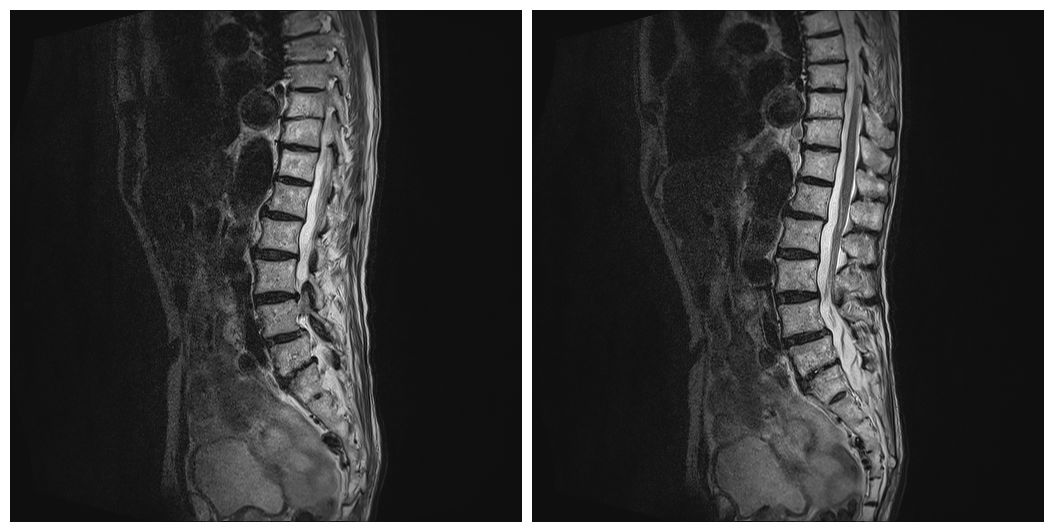

图2 12月06日腰椎MRI复查结果

腰椎多发异常信号,较前片明显好转(L4-5椎体椎间隙变窄,椎间盘T2信号减低,周围片状长T1长T2信号,压脂T2呈高信号,信号强度较前明显减低,周围软组织水肿信号较前吸收)。腰椎退行性变,L4椎体不稳。